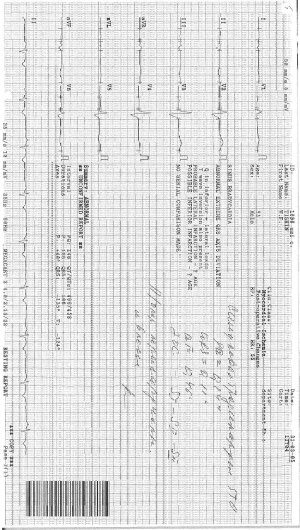

Утром он просыпается с давлением 100/60 и пульсом 47. В течении дня в спокойном состоянии пульс не выше 58.

Утром он просыпается с давлением 100/60 и пульсом 47. В течении дня в спокойном состоянии пульс не выше 58.